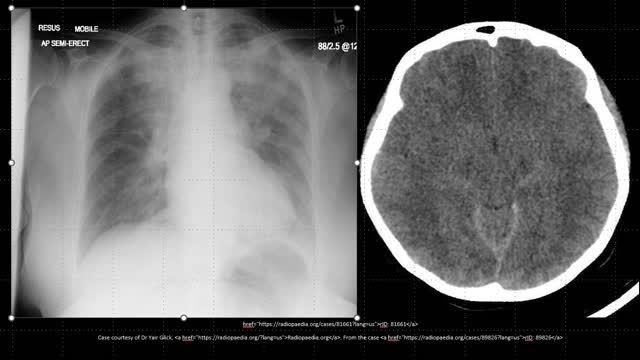

what is the next step in management of this ANCA positive microscopic polyangiitis with both renal and pulmonary involvement.